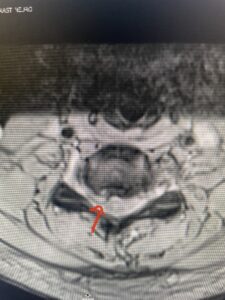

This 47-year-old male who four months prior was lifting weights developed sharp pain in his neck. After that he developed progressive numbness in his arms, neck pain and headache. He said that the right arm was worse than the left. On examination the patient had long tract weakness on the right side which included his triceps, finger extensors, hip flexors, and dorsiflexors. The patient did not have hyperreflexia. MRI (Fig. 2) demonstrated a massive, extruded disc herniation with severe cord compression. The patient because of progressive myelopathy and spinal cord compression was indicated for anterior cervical discectomy and fusion at C4-5 (Fig. 3). Patient had significant improvement of weakness and numbness post operatively.

Fig. 2a Sagittal T2-weighted cervical MRI demonstrating large C4-5 herniated disc with spinal cord compression (red arrow)

Fig: 2b Axial T2-weighted cervical MRI demonstrating spinal cord compression from C4-5 herniated disc (red arrow)